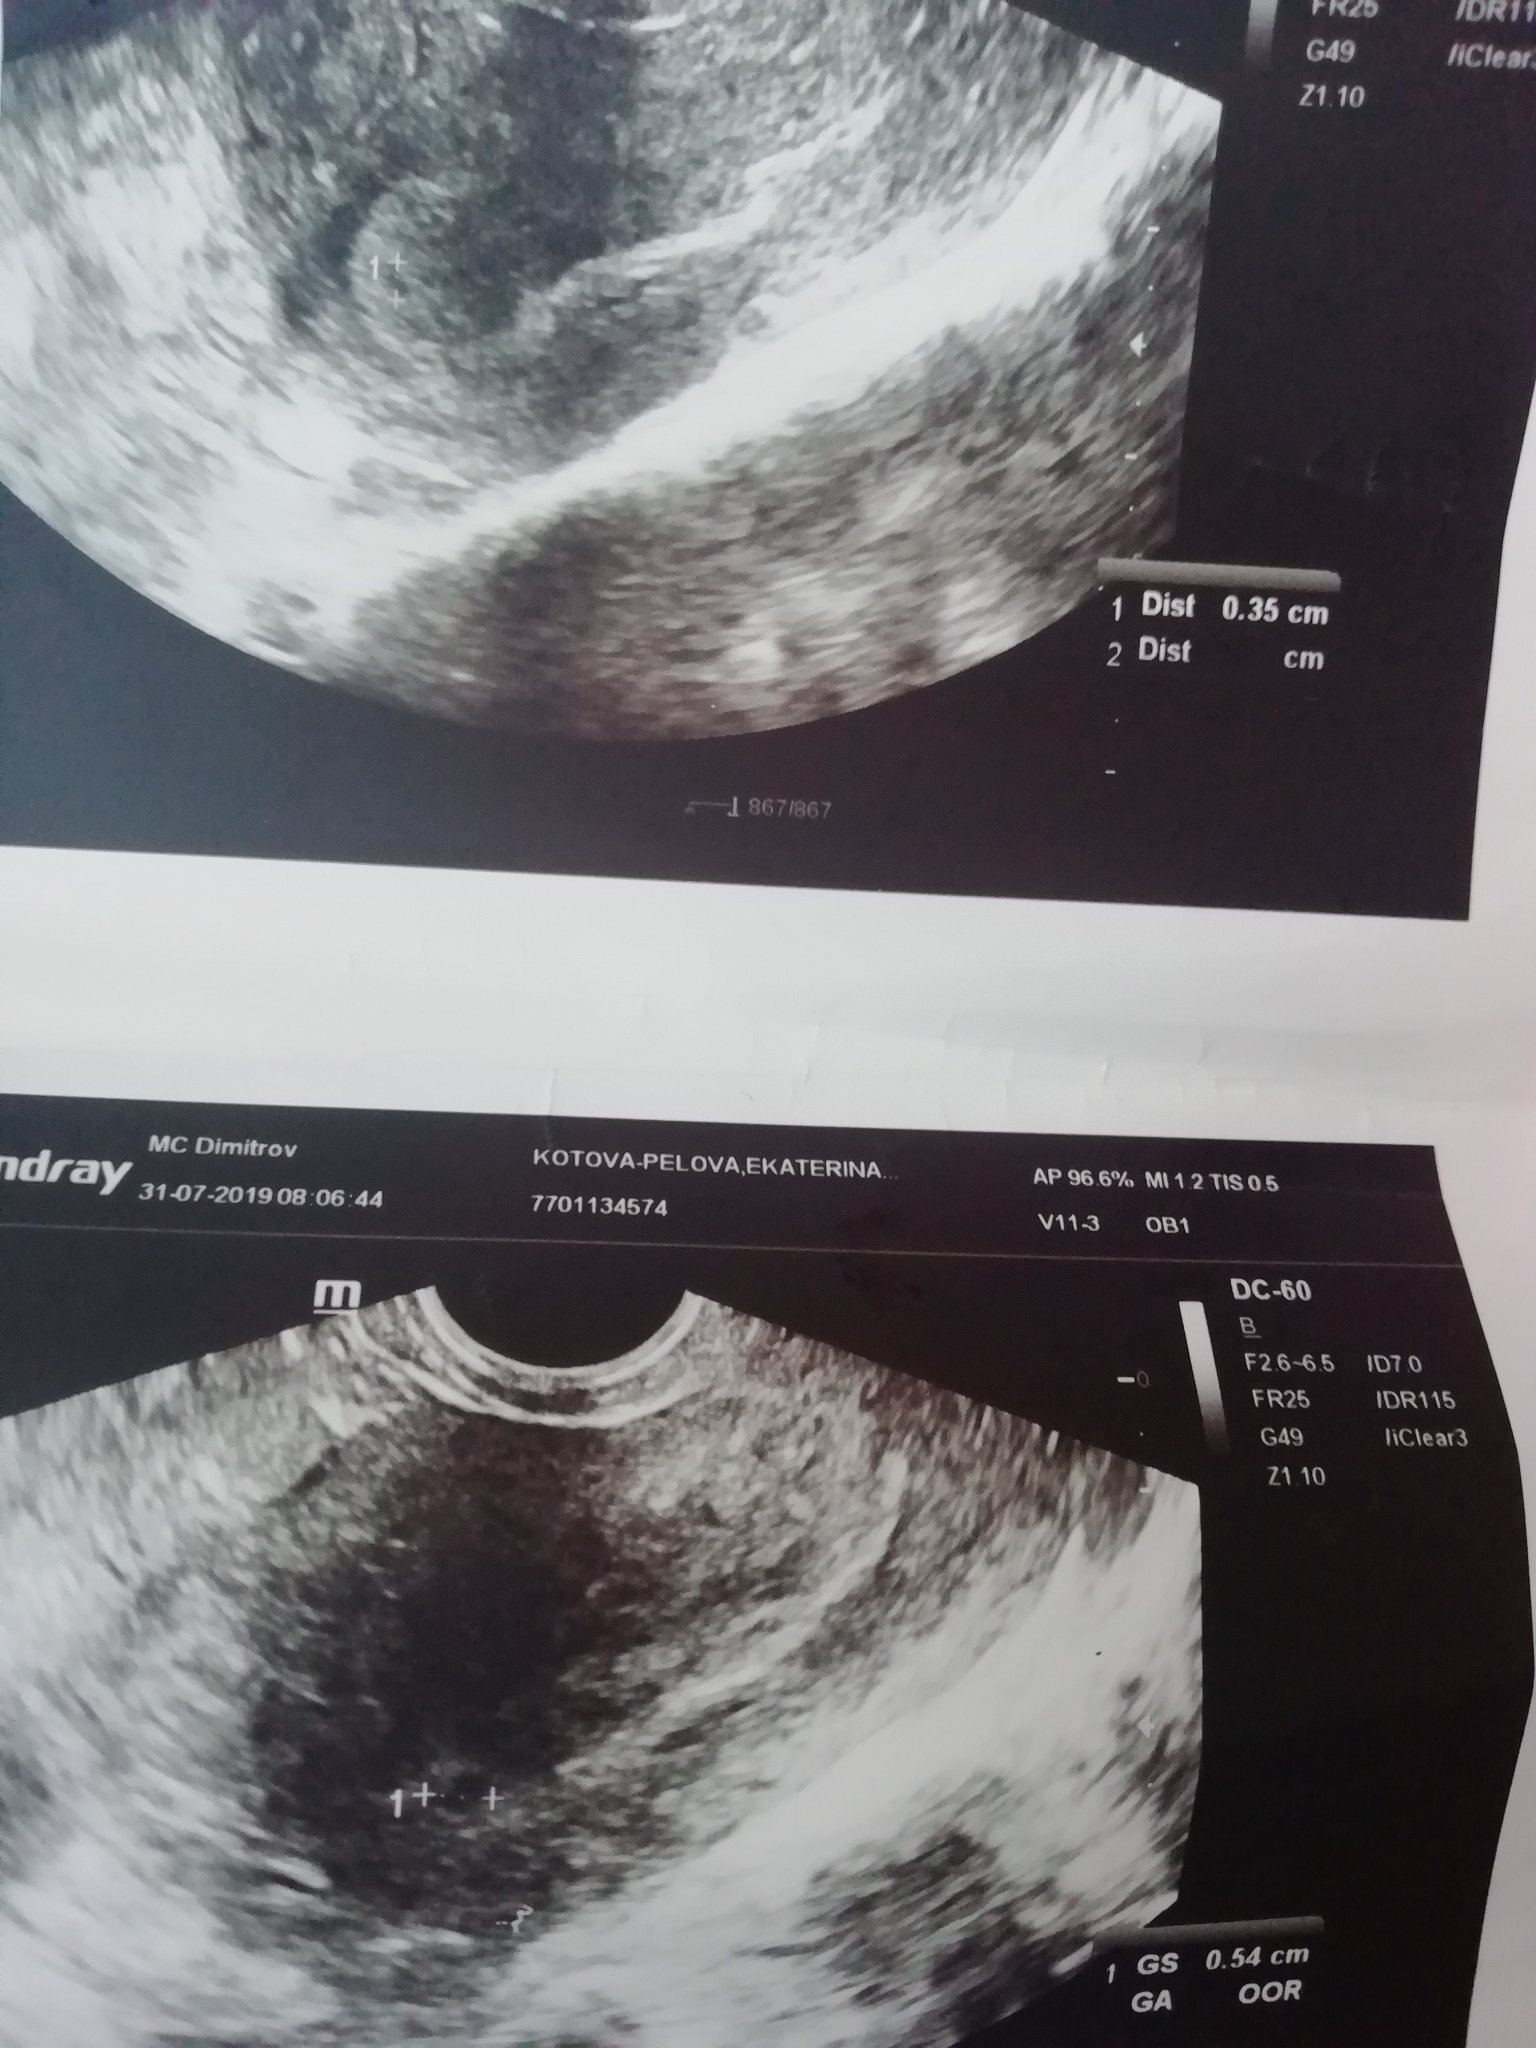

Как се случва точно няма как да ви обясня,факт е че имаше сак в матката,с жълтъчно мехурче,което си растеше съвсем нормално. В 8ма седмица след обстоен преглед откриха ембриончето със сърдечна дейност в яйчника,честно казано не задавах много въпроси тогава как и защо,бях съсипана. Но го видях с очите си,това което си коментираха лекарите беше за така наречения псевдо сак и в последствие се разрових за инфо и в нета.